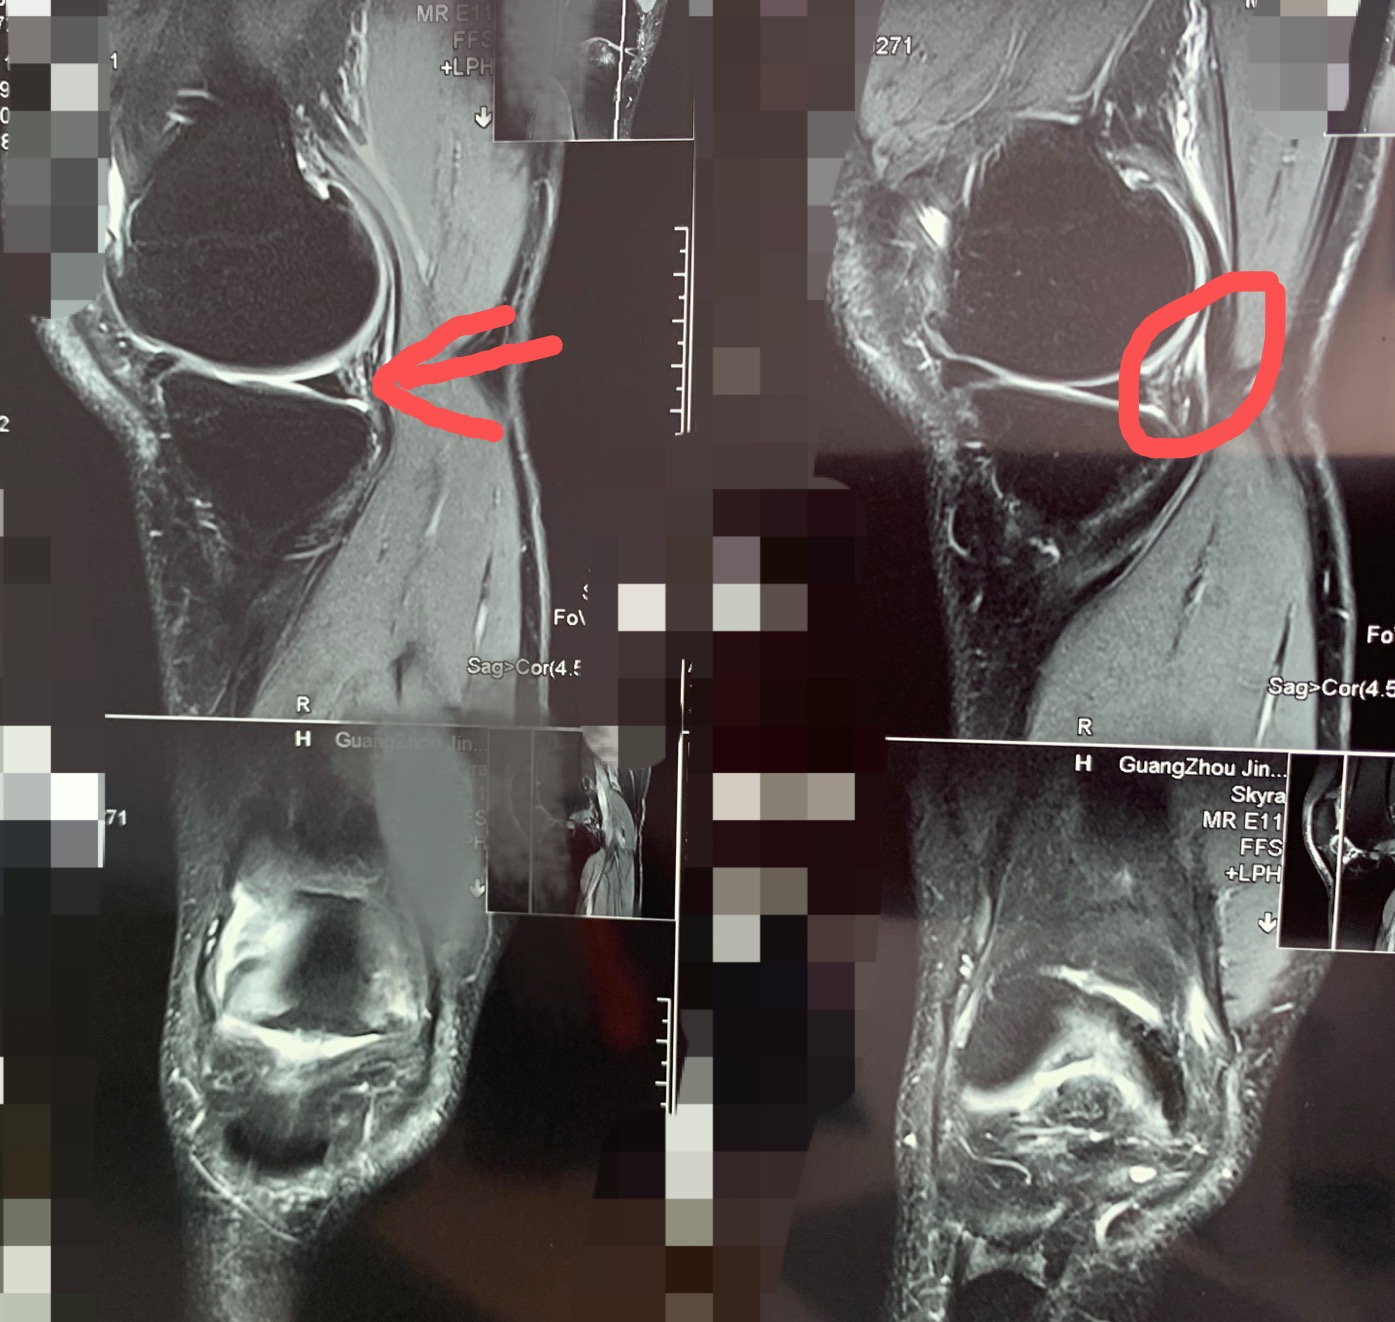

相比十字韧带的损伤,半月板的撕裂更常见。我最近在门诊刚好就接诊了这样的一位朋友。这位朋友是40多岁的运动爱好者,两边膝盖都有事,我们具体看看这位朋友的情况。

先看右膝

右膝踢球后旧伤,最近几个月屈伸时突然有卡住的感觉,痛,我查体发现不能完全伸直,关节间隙有压痛,不能完全伸直。其实这是很典型的半月板损伤表现。

以下是他的磁共振

红色指的地方就是半月板后角损伤的地方

再看左膝

左膝是半年前踢球时扭到了,随后出现打软腿,上下楼梯时发力都发不了。我查体一看,前后稳定性非常明显的不稳,前抽屉试验阳性的,看了磁共振,明显的前十字韧带断裂了。

前十字韧带断裂明显